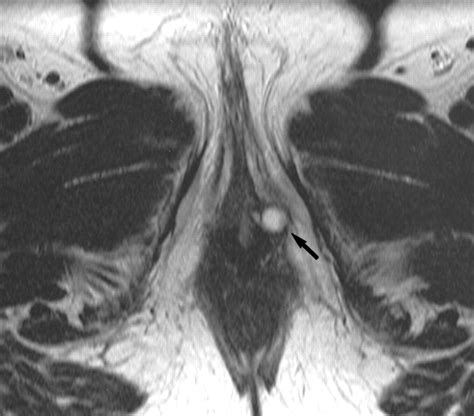

The Skene glands, also known as the paraurethral glands, are located on the anterior wall of the vagina, specifically around the lower end of the urethra. They are considered the female equivalent of the prostate gland in males. These glands are responsible for secreting a lubricating fluid that helps keep the urethral opening moist. When the ducts of these glands become obstructed or infected, the fluid cannot drain properly, leading to the formation of a Skene Gland Cyst.

While many people may go their entire lives without realizing they have these glands, issues arise when the ductal opening is blocked. This blockage causes the fluid to accumulate, eventually forming a visible or palpable lump. These cysts can vary in size, ranging from a small pea to a larger, more painful growth.

If you suspect you have a cyst, the best approach is to visit a healthcare provider, such as a gynecologist. Diagnosis is usually straightforward and involves a physical pelvic examination. In some instances, if the doctor suspects an infection or a more complex mass, they may order imaging tests like an ultrasound or a biopsy to rule out other conditions.